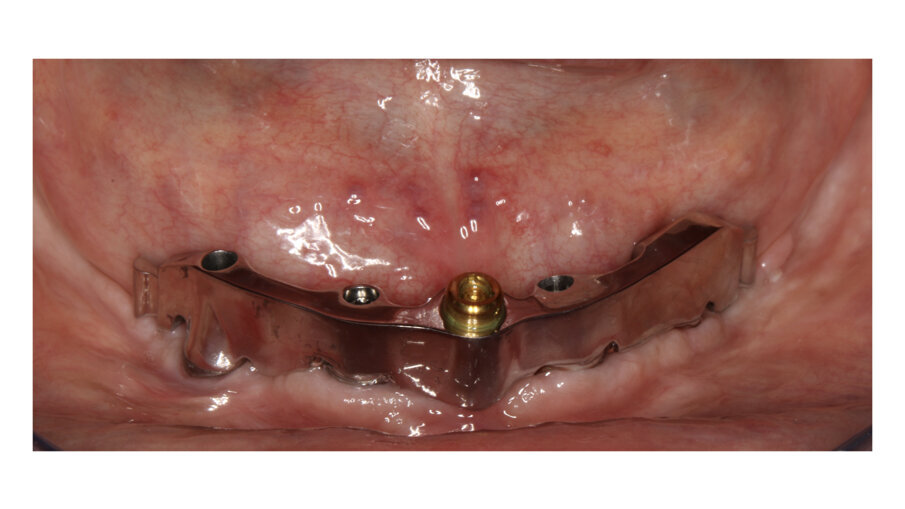

In this case, a patient presented with extremely atrophic bone in the mandible, with four short implants placed between the dental nerve foramen (Figs, 10a, 10b). After some time, patients wearing this kind of restoration with prefabricated teeth, their muscle activity increase considerably, which very often leads to fracture or debonding of the prefabricated teeth (Fig. 12). A combination of a rigid metal structure over the telescopic bar and a thimble structure made of PEEK (Fig. 13, 14) works as base for the final restorations. These were milled out of a BRILLIANT Crios disc either as single tooth units or bridges and cemented on the thimble structure (Figs. 15-17). Using BRILLIANT Crios instead of prefabricated teeth, we can increase the strength of the restoration, have good aesthetics and keep the weight low for this kind of prosthesis.

Figs. 10a and 10b : Patient with extremely atrophic bone in the mandible with four short implants placed between the dental nerve foramen

Fig. 11: Telescopic bar with retentions for the secondary structure